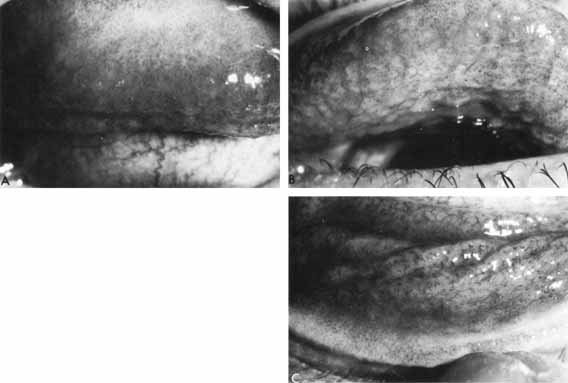

The follicular conjunctivitis of primary herpes is associated with a regional adenitis. Typically, the ipsilateral preauricular lymph node is slightly enlarged and a little tender. Swollen lids and a primary skin lesion are often readily apparent (Figs. 3 and 4), but on occasion only a careful search will reveal the single or grouped vesicles of crusted ulcers (Figs. 5 and 6) hidden among the lashes or in the intermarginal strip. Similar lesions may be located elsewhere on the face or at the mucocutaneous junction of the mouth, in the nose, or on the trunk, and they may be easily missed unless a specific search is made. In nearly one fourth of cases, no cutaneous lesions are present.35 The conjunctiva is injected and edematous. Follicles develop, especially in the fornices, and extend to the tarsal areas (Fig. 7);they rarely occur at the limbus. Small subconjunctival ecchymoses are not uncommon and phylectenule-like lesions may develop on the globe (Fig. 8).

Fig. 7 Acute follicular conjunctivitis in primary herpetic infection: A Upper tarsus, B Upper fornix, C Lower fornix. (Courtesy of Dr. S. Darougar)

Fig. 8 Chemosis and ecchymosis of bulbar conjunctiva. (Courtesy of Dr. S. Darougar)